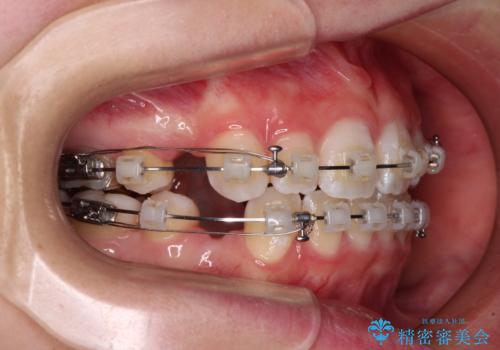

- クリアブラケット

- 治療期間

- 1年6ヶ月

- 前歯の出っ歯と口元の閉じにくさを気にして来院された患者様です。

口元を積極的に引っ込めるために、上下左右の小臼歯4本を抜歯することとしました。